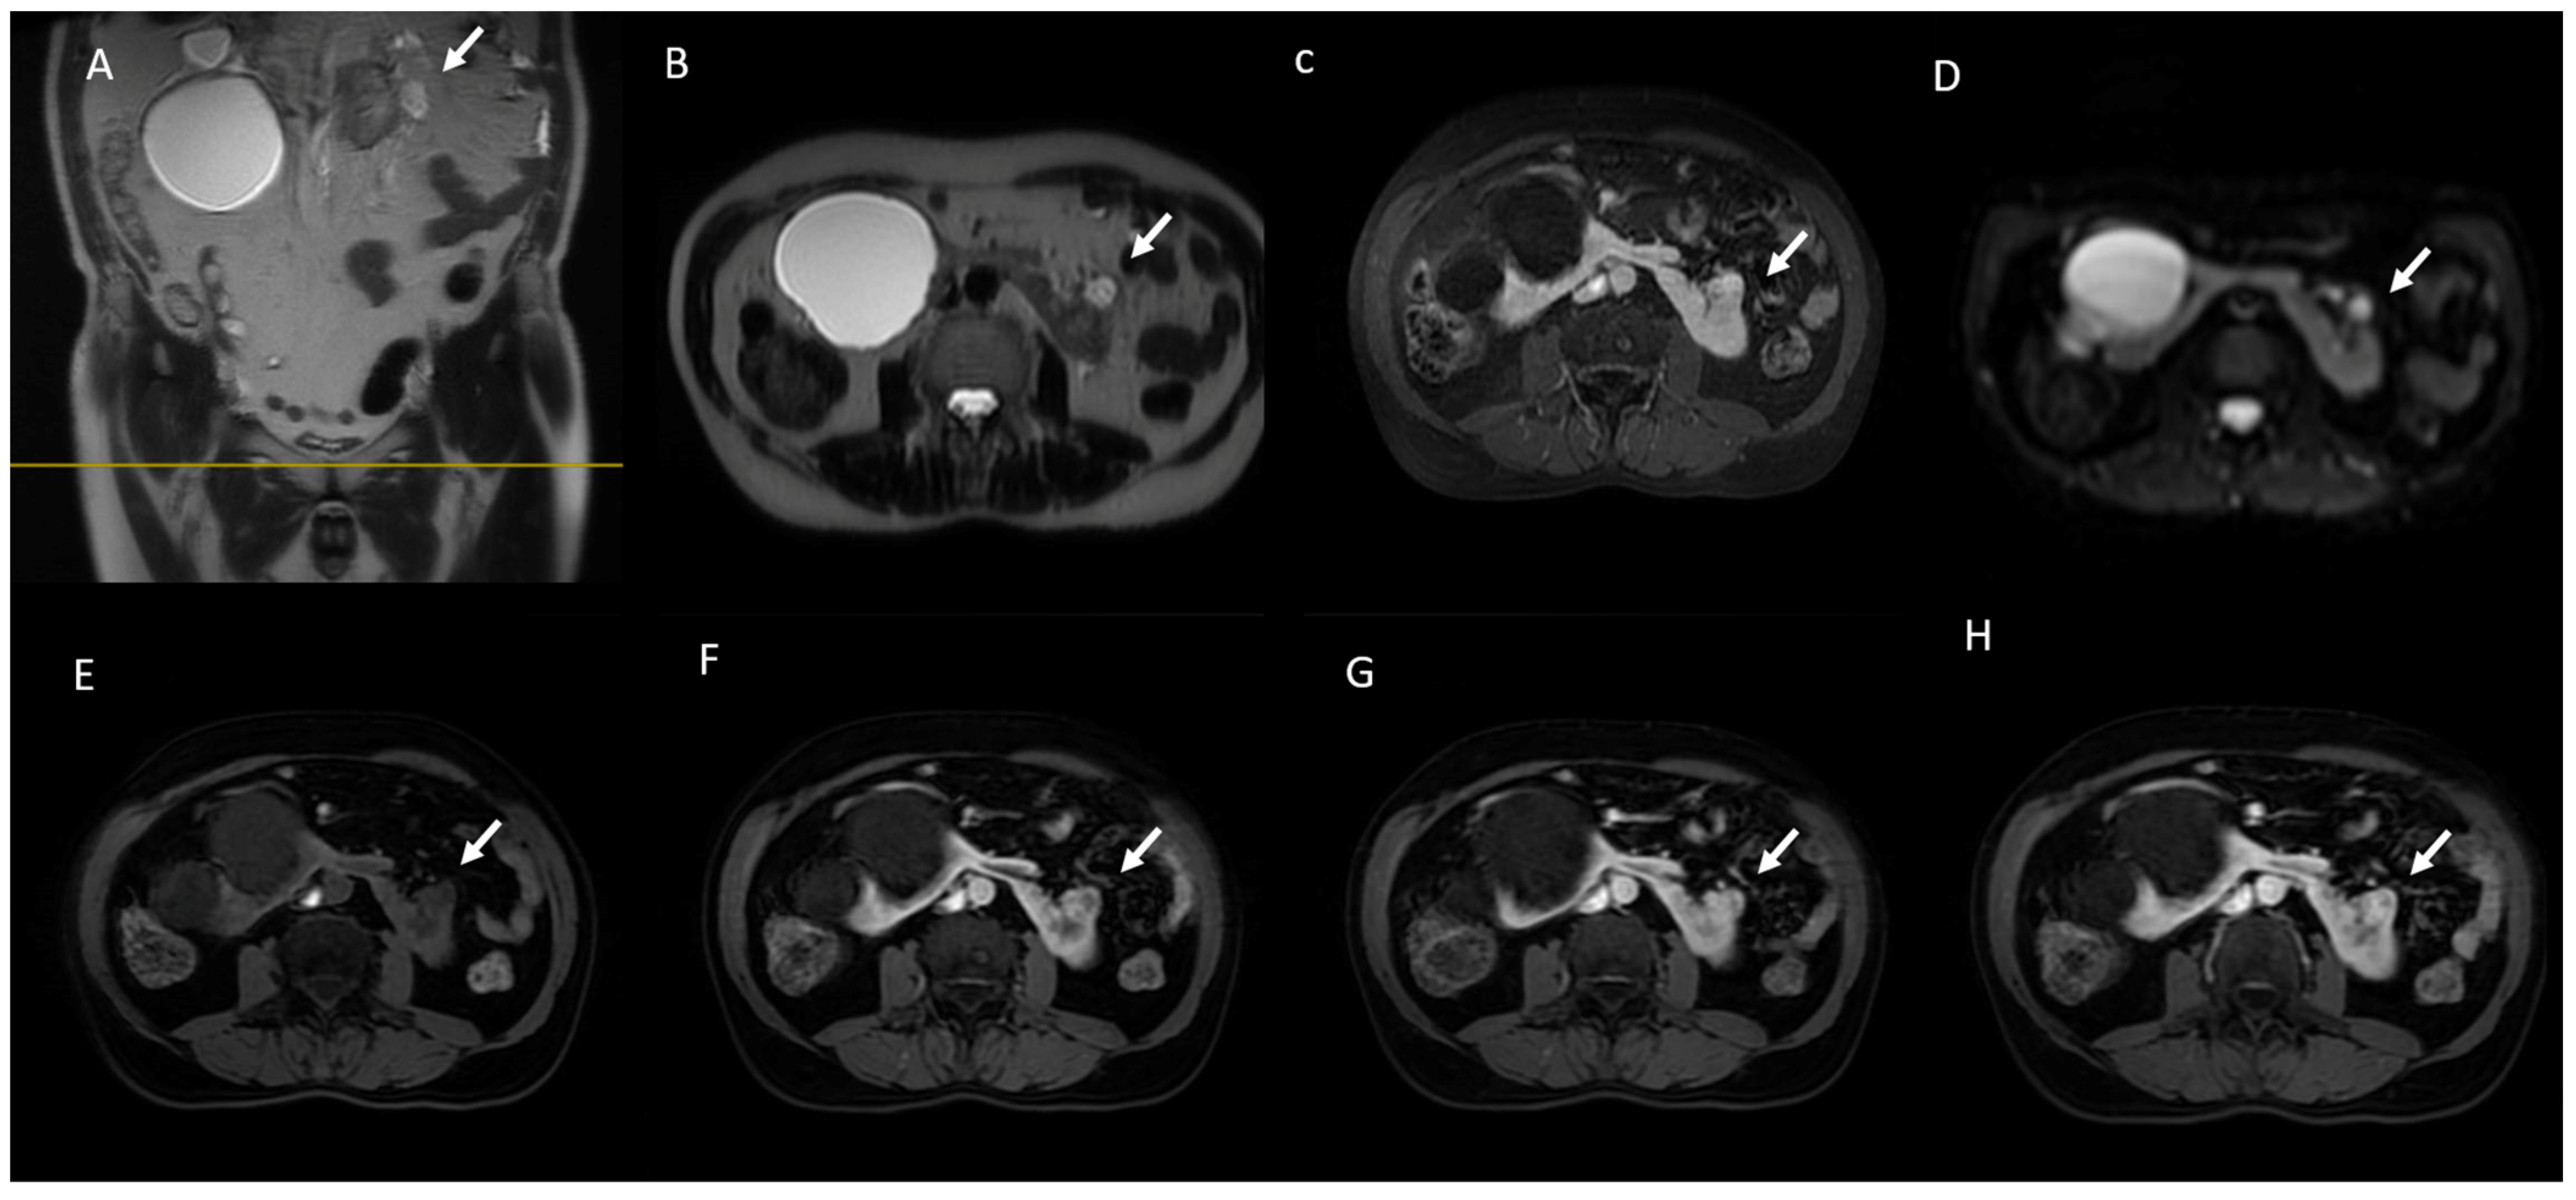

6. MRI Assessment

6.3. Diffusion-Weighted Imaging

6.4. Gadolinium-Enhanced Sequences